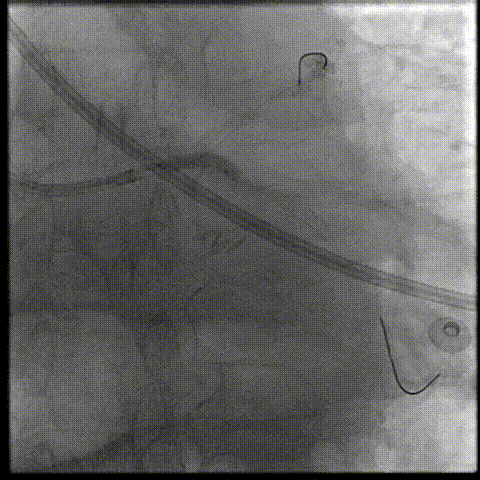

对LAD近段-LM 进行IVUS检查,提示重度钙化病变

针对LAD近段-LM 选择shockwave3.5*12mm,间断触发脉冲,每5个脉冲为一组,只4atm治疗,省略6atm扩张,每次回撤Guiding,共8个周期;

LAD开口前后IVUS

LM前后IVUS

选择shockwave3.0x12mm于LCX近段-LM ,间断触发,8个周期

LCX开口前后IVUS